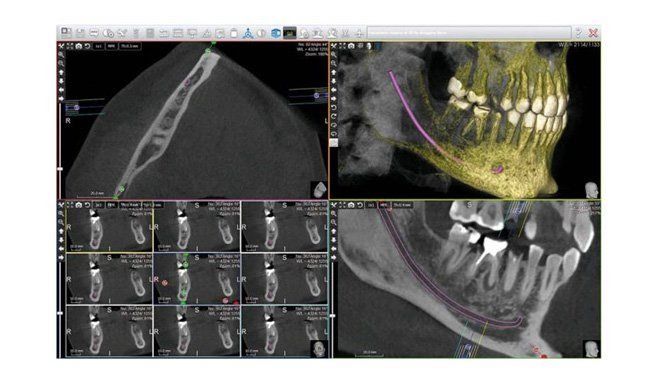

La TC Cone Beam (CBTC) è un’indagine che consente di studiare con alta risoluzione le arcate dentarie del paziente e di visualizzare tutte le strutture anatomiche adiacenti.

Presso il CE.DI.R. di Marcianise è possibile svolgere la CBTC su prenotazione. Rispetto a un esame TC tradizionale, questa tecnologia offre il vantaggio di esporre il paziente a una dose ridotta di radiazioni e di ottenere, al contempo, una migliore risoluzione tridimensionale delle immagini.